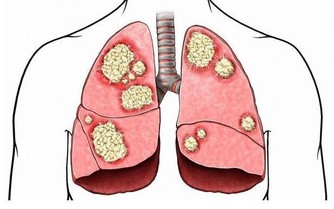

同時對於抑制人體癌細胞的生成及轉移有很大的作用。適合全家人一起食用,老少皆宜!